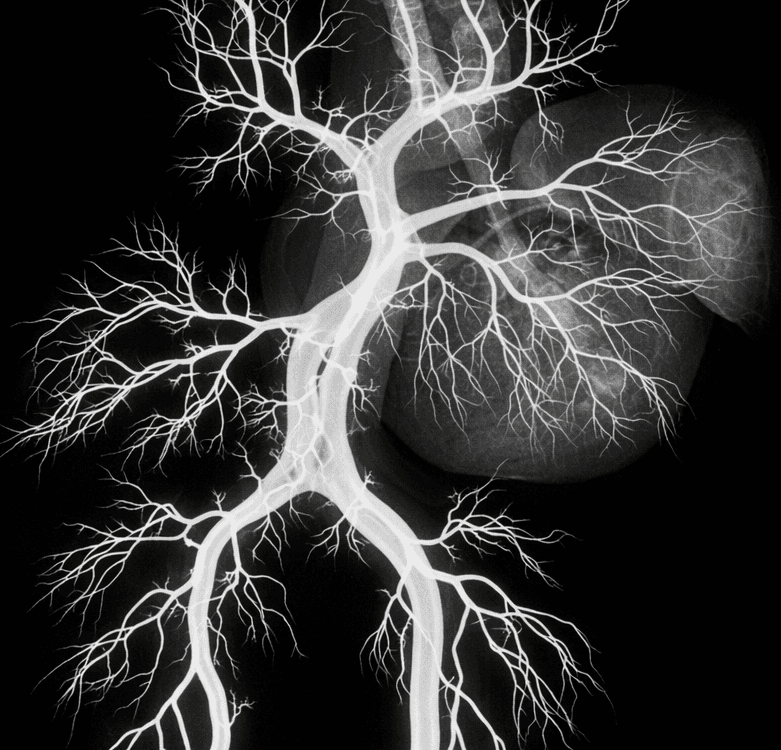

Ordering and interpretation of appropriate cardiovascular blood tests and imaging studies